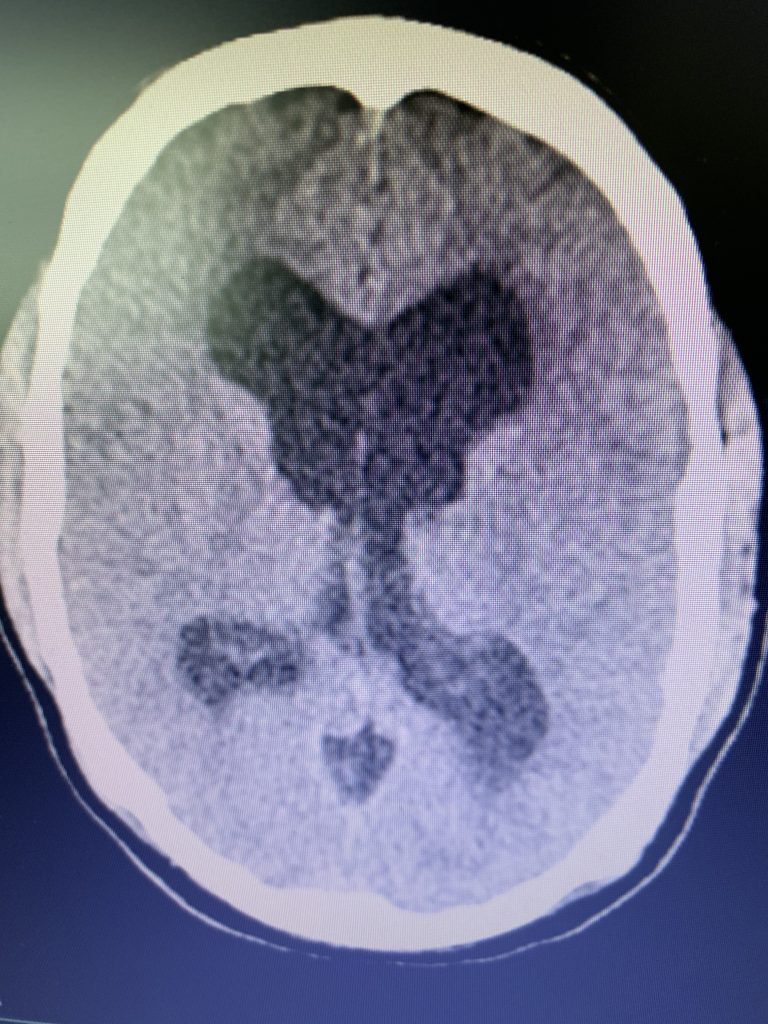

On initial examination, the patient was neurologically intact without complaints of headache. His imaging; however, did show hydrocephalus, most notably the lateral and third ventricles with a normal sized fourth ventricle. Given that the patient had no complaints, a decision was made to follow this expectantly and he was referred for a neuro-ophthalmologic evaluation, which confirmed no evidence of papilledema. MRI was otherwise negative.

Prior to shunting, a head CT was obtained and the head CT in addition to documenting a patten of obstructive hydrocephalus suggested a possible mass lesion compressing the aqueduct at its inferior aspect. Figure #1 demonstrates the hydrocephalus and the possible lesion. A decision was made at this point that the patient had obstructive hydrocephalus that was now symptomatic and he was taken for a laparoscopic-assisted ventriculoperitoneal shunt.

Answer: This is most likely a benign intraaxial low-grade glioma. These tend to be indolent. He will be followed up with serial MRIs with gadolinium and unless there is a growth or otherwise change in the lesion, this will be followed expectantly.